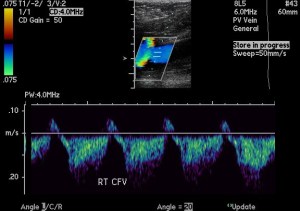

Doppler color ultrasound of the right common femoral vein with waveform.